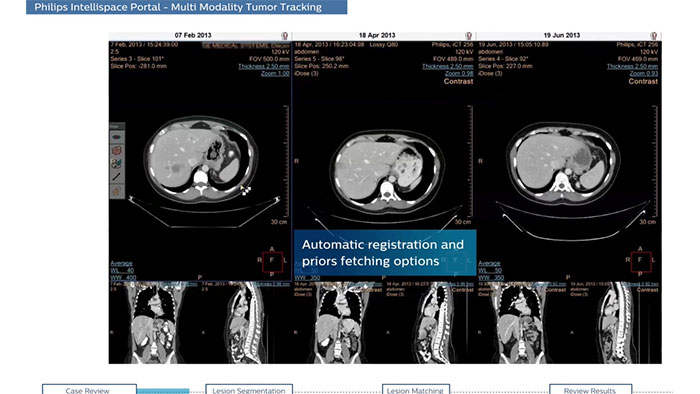

Streamlined workflow for follow up and analysis of oncology patients

Multi Modality Tumor Tracking (MMTT) is a post processing software used to monitor disease state and assess treatment response.

Benefits